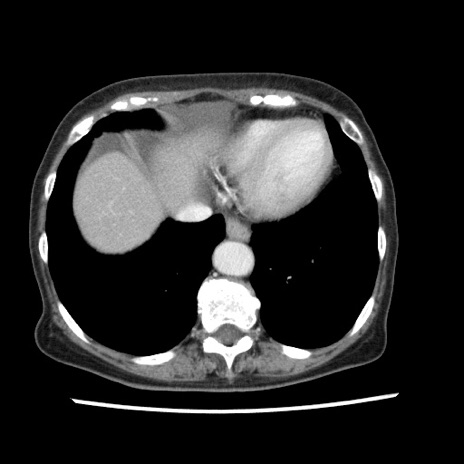

冠状断像

矢状断像

【症例】80歳代女性

【主訴】腹痛

【現病歴】8時間前から腹痛あり来院。

【既往歴】糖尿病、脂質異常症、子宮体癌にて子宮全摘術

【身体所見】意識清明・会話良好だが腹痛で苦悶様、全腹部にわたって反跳痛と圧痛あり

【データ】WBC 13600、CRP 0.14、LDH 224、CK 90